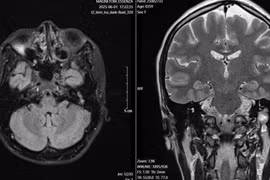

Sau một đêm ngủ phòng điều hòa (máy lạnh), bà H.T.T. 47 tuổi (Phú Thọ) bất ngờ phát hiện mắt phải nhắm không kín, miệng méo sang trái, ăn uống rơi vãi, đi khám được chẩn đoán liệt mặt phải do lạnh.

Tỉnh dậy sau một đêm ngủ phòng điều hòa (máy lạnh), bà H.T.T. 47 tuổi (Phú Thọ) bất ngờ phát hiện mắt phải nhắm không kín, miệng méo sang trái, ăn uống rơi vãi, đi khám được chẩn đoán liệt mặt phải do lạnh